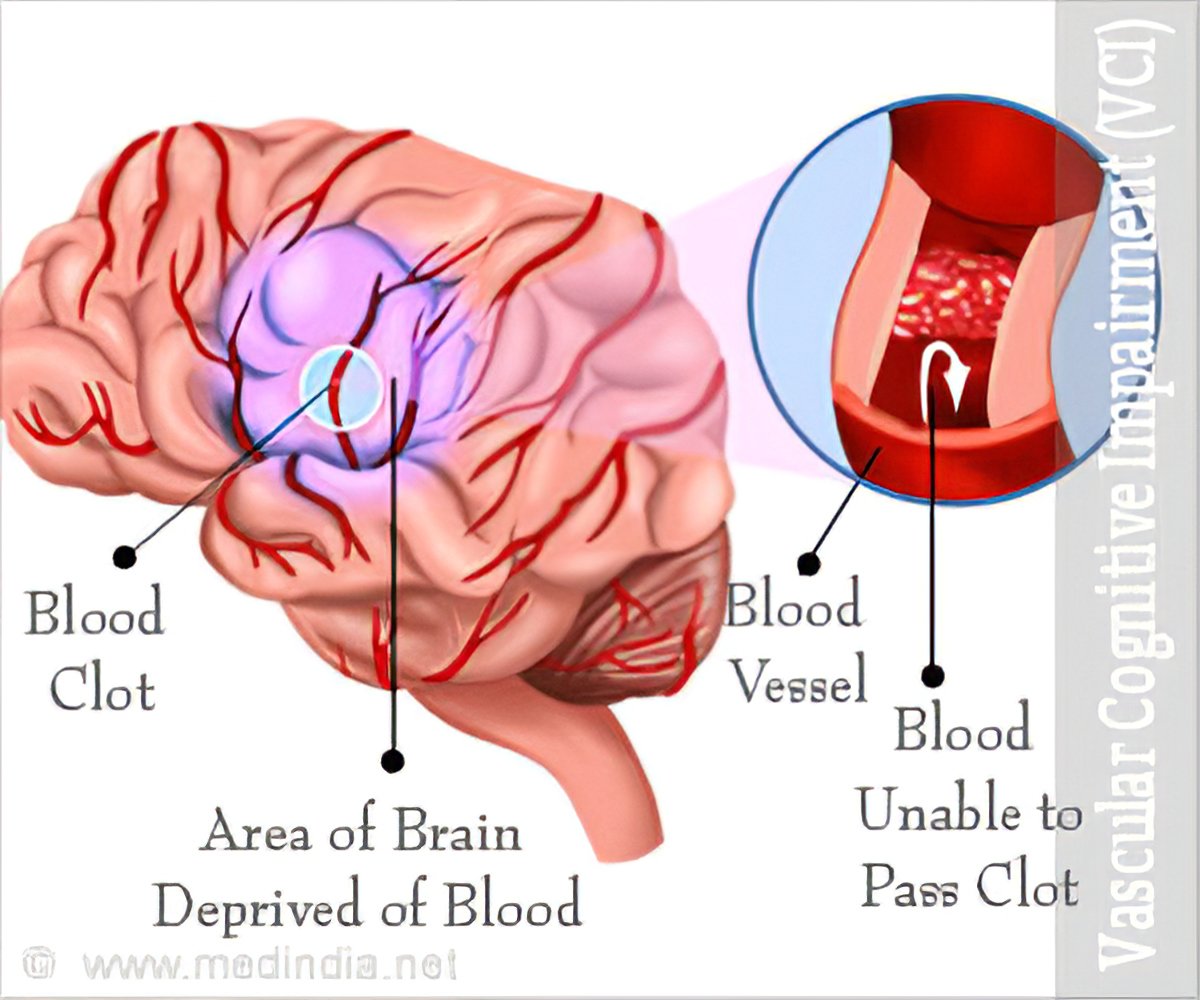

[PDF] The Pathobiology of Vascular Dementia | Semantic Scholar

What is Vascular Dementia and how does it differ from Alzheimer’s …

Vascular dementia | Vascular dementia, Dementia, Alzheimers

Vascular dementia – The Lancet

Vascular Dementia – Causes, Types, Symptoms, Diagnosis, Treatment …

Stages Of Vascular Dementia Check more at http://www.nhprimecare.org …